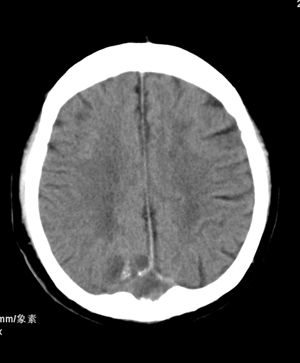

标题: CT13600:男,70,头晕思睡7天,BP160/100MMHG,颅N(-) [打印本页]

肢体活动肌力均正常。临床印象:脑血管病变。ct意见:脑软化灶,腔梗,请看看枕部病变是脑膜瘤,血管畸形还是其它

颅骨吸收破坏,病灶密度不均,周围见低密度水肿带,多考虑恶性脑膜瘤。

1.右基底节区脑软化灶。

2.右顶后部病变,脑膜瘤可能性大。

建议:强化扫描。

枕骨骨质吸收破坏,局部病灶密度不均,周围见低密度水肿带,考虑脑膜瘤,建议增强扫描。

建议:强化扫描。不除外静脉窦血栓形成